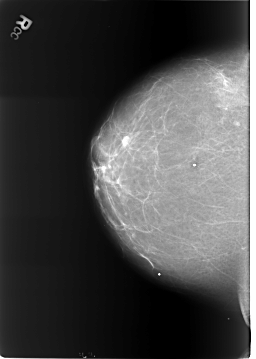

B_3241_1.RIGHT_MLO

DENSITY 2

LEFT_CC LINES 5720 PIXELS_PER_LINE 4088 BITS_PER_PIXEL 12 RESOLUTION 50 OVERLAY

LEFT_MLO LINES 5840 PIXELS_PER_LINE 3888 BITS_PER_PIXEL 12 RESOLUTION 50 OVERLAY

RIGHT_CC LINES 5744 PIXELS_PER_LINE 4088 BITS_PER_PIXEL 12 RESOLUTION 50 NON_OVERLAY

RIGHT_MLO LINES 5704 PIXELS_PER_LINE 4128 BITS_PER_PIXEL 12 RESOLUTION 50 NON_OVERLAY

ABNORMALITY 2

LESION_TYPE CALCIFICATION TYPE LUCENT_CENTER-PUNCTATE DISTRIBUTION N/A

ASSESSMENT 2

SUBTLETY 5

PATHOLOGY BENIGN_WITHOUT_CALLBACK